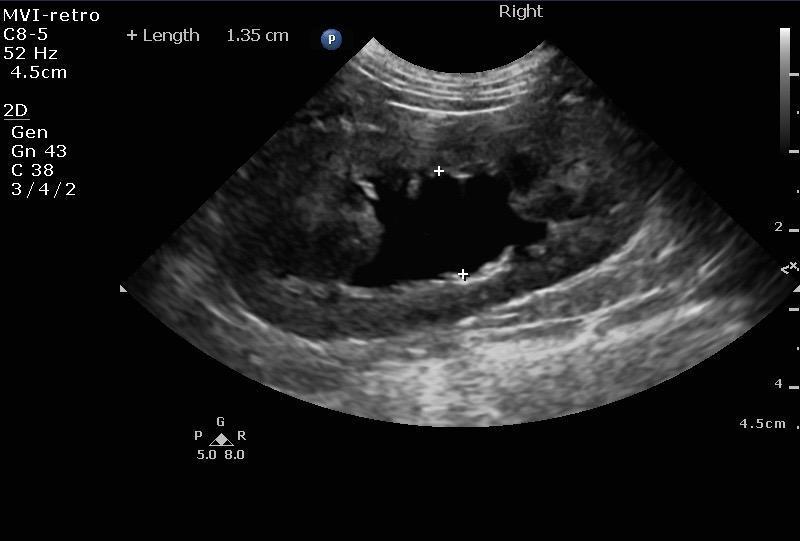

Mild pyelectasia was noted in the left kidney at 4.62 cm and pyelectasia is at 1.01 cm. The left kidney presented a slight amount of perinephric free fluid suggestive for inflammation. Right kidney presented moderate pyelectasia 1.35 cm with obstructed proximal ureter calculus 0.5 cm. Right kidney measured 5.36 cm.

The urinary bladder and trigone presented normal wall thicknesses with anechoic urine and normal tone. Pelvic urethra was imaged 3 cm beyond the cystourethral junction. No uroliths or sediment were visualized. No evidence of inflammatory or neoplastic changes were noted. Left ureter in this patient presented 0.7 cm calculus and a separate 0.25 cm calculus obstructive the left ureter midway between the kidney and the bladder.